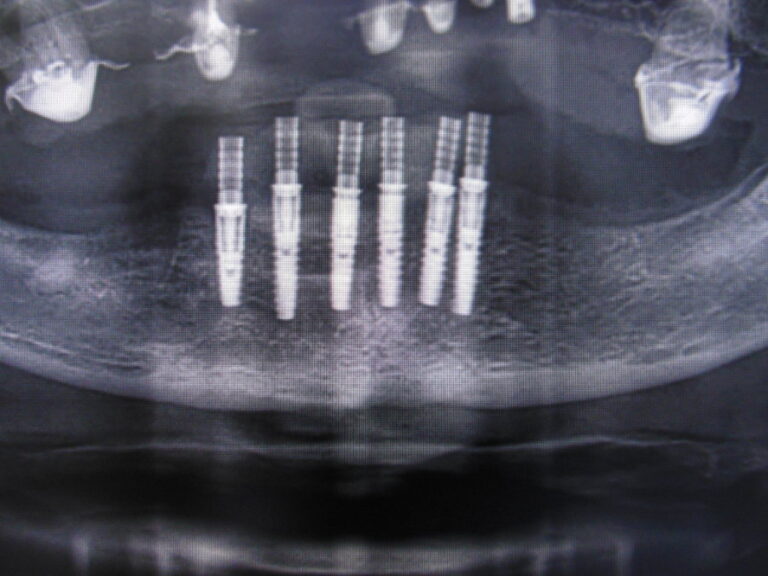

Implanty zygomatyczne